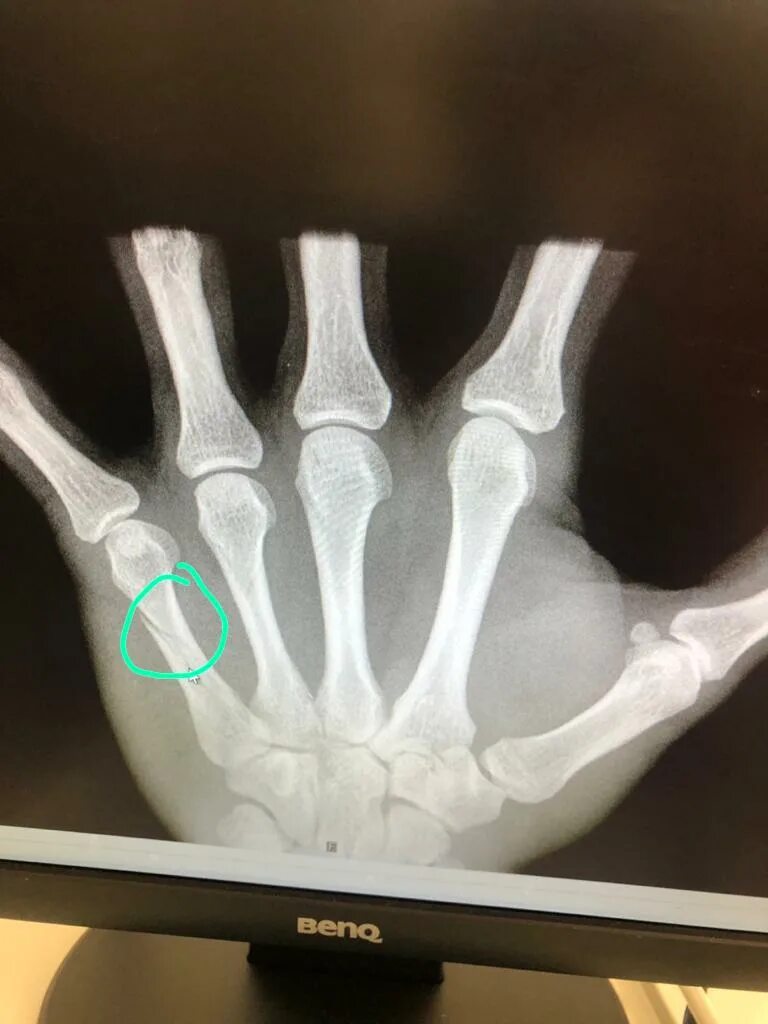

Перелом пятой пястной кости